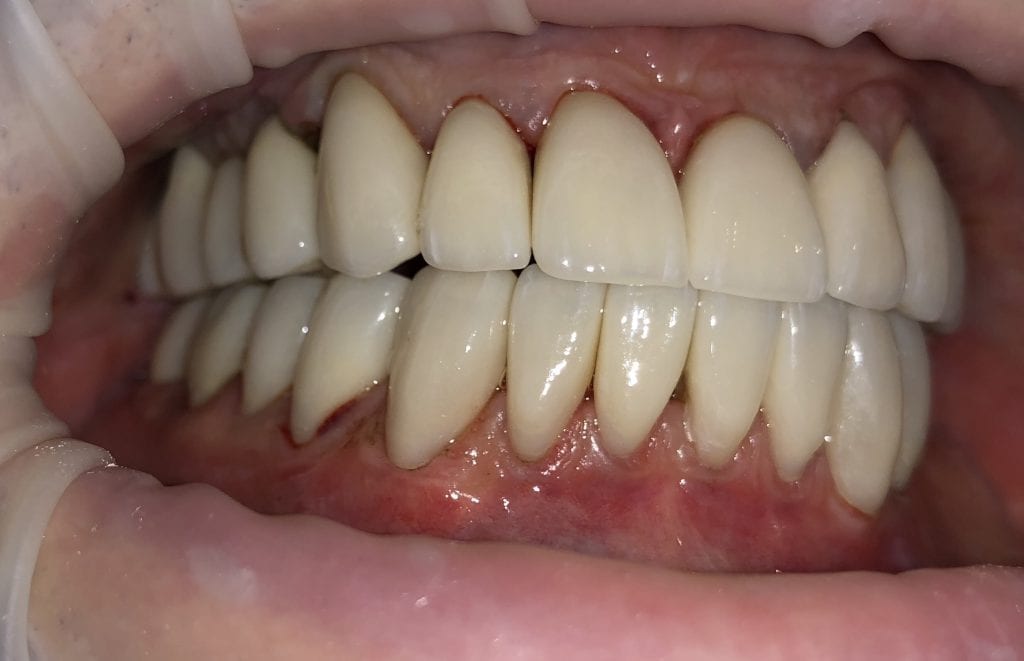

IMMEDIATE POST-OP PHOTOS AND VIDEO WITH IPHONE CAMERA